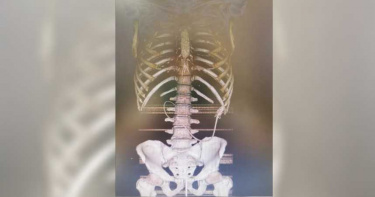

14歲少年「菊花炸裂」高爾夫球整顆塞肛門 醫6招猛攻後庭取不出

菊花殘,滿地傷,你的笑容已泛黃……人類出於性滿足,放進肛門裡的東西千奇百怪,澳洲一名14歲少年,居然把「整顆高爾夫球」從肛門塞入體內,卻卡在深處無法取出,於是前往急診求助,最終靠著超大量瀉藥才解決困境。從X光照可見,這名少年的乙狀結腸(sigmoidcolon),也就是大腸和直腸連接處出現白色異物,看起來很像雞蛋,實際上卻是一顆完整的高爾夫球。綜合外媒報導,這名少年並沒有任何不適,但無法透過排便自行移除,因此感到驚慌,最後鼓起勇氣告知母親,並被緊急帶往皇家阿德萊德醫院(Royal Adelaide Hospital)。醫師們嘗試各種「激進」手段,像是使用吸盤、套索、四爪夾等6種方法,足足耗了2個多小時後,但高爾夫球依然頑強地待在原地,由於家屬希望不要再採取物理移除方式, 醫療團隊只好開立1公升的瀉藥, 未料3小時後證實高爾夫球成功排出,而且沒觀察到腸道受損證據。醫生也把這起特殊案例發表於《外科病例報告》。醫療團隊在論文中提到,由於高爾夫球具特殊屬性,包括大尺寸、球體形狀、表面小凹洞及不可壓縮性,阻礙了形成吸力的密封環境,因此若試圖從結腸取出,會構成技術性挑戰。醫療團隊建議,若未來遇到類似病例,且患者沒有腸道功能障礙,或許可以嘗試給予瀉藥,在不需手術干預的狀況下排出異物。至於這名少年排出高爾夫球後,臨床表現保持良好,並在同一日辦理出院,但也被嚴厲警告,未來不要再往直腸亂塞東西。醫療團隊只好開立1公升的瀉藥, 未料3小時後證實高爾夫球成功排出。(圖/翻攝自@nypost推特)